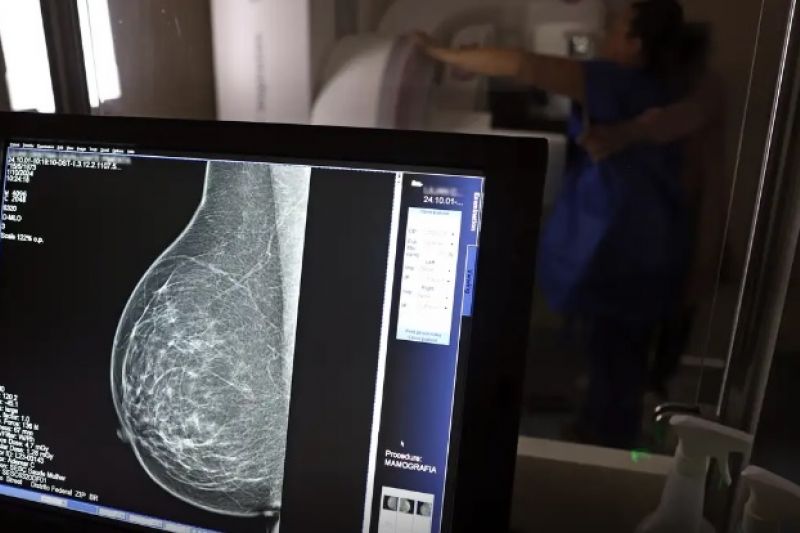

Em junho deste ano, 77.243 brasileiras aguardavam por uma mamografia no Sistema Único de Saúde (SUS). Santa Catarina é o estado com mais mulheres na fila de espera, cerca de 17 mil. Em seguida, aparecem São Paulo (15 mil) e Rio de Janeiro (12,5 mil). Juntos, os três estados somam 56% do total de pacientes à espera do principal exame para detecção do câncer de mama. Os dados foram divulgados nesta quinta-feira (31) pelo Colégio Brasileiro de Radiologia e Diagnóstico por Imagem (CBR).

Segundo a entidade, em alguns locais do país, o tempo de espera por uma mamografia na rede pública pode chegar a 80 dias. O exame, quando realizado em tempo hábil, permite a detecção precoce de alterações mamárias, aumentando as chances de tratamento bem-sucedido e reduzindo a necessidade de intervenções invasivas e onerosas. “Os números revelam parte da sobrecarga no SUS e devem ser levados em conta, especialmente pelos recém-eleitos nas eleições municipais, na formulação e manutenção de políticas de saúde pública”, avaliou o CBR.

Relatório recente publicado pelo Instituo Nacional de Câncer (INCA) sobre o controle do câncer de mama no Brasil aponta que longos períodos entre a solicitação do médico e a emissão do laudo podem dificultar a adesão da população ao rastreamento da doença. Em 2023, 48,8% das mamografias de rastreamento tiveram laudos liberados em até 30 dias após a solicitação do exame. Cerca de 36% dos laudos, entretanto, foram liberados com mais de 60 dias.